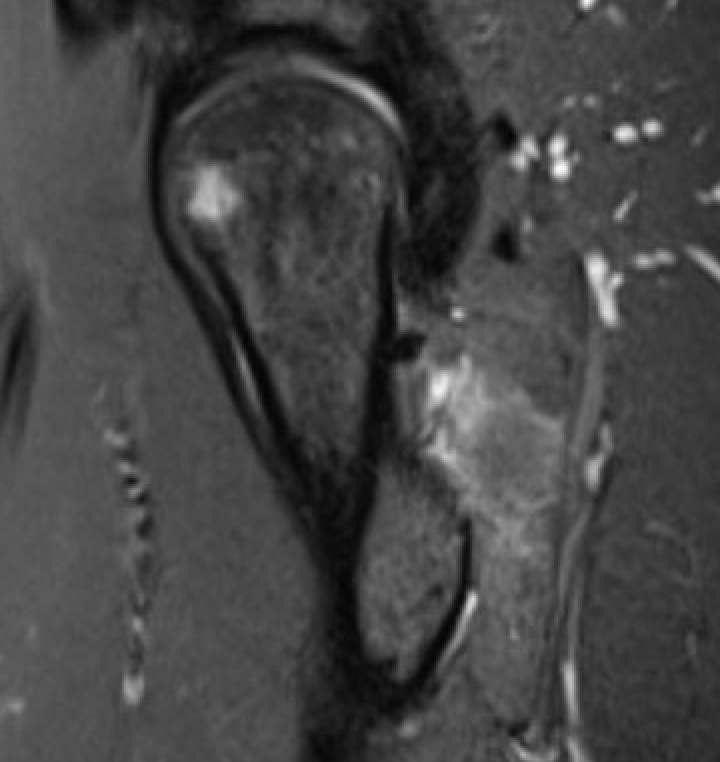

MRI

Reduced ischiofemoral space - distance between the lesser trochanter and the ischial tuberosity

Reduced quadratus femoris space - distance between hamstring tendon and iliopsoas

Inflammation / edema in quadratus femoris +/- fatty degeneration

Singer et al Skeletal Radiol 2015

- systematic review of 190 hip MRI of patients with ischiofemoral impingement

- compared to controls

- ischiofemoral space < 15 mm: sensitivity 77%, specificity 81%, accuracy 78%

- ischiofemoral space < 10 mm: sensitivity 79%, specificity 74%, accuracy 77%.